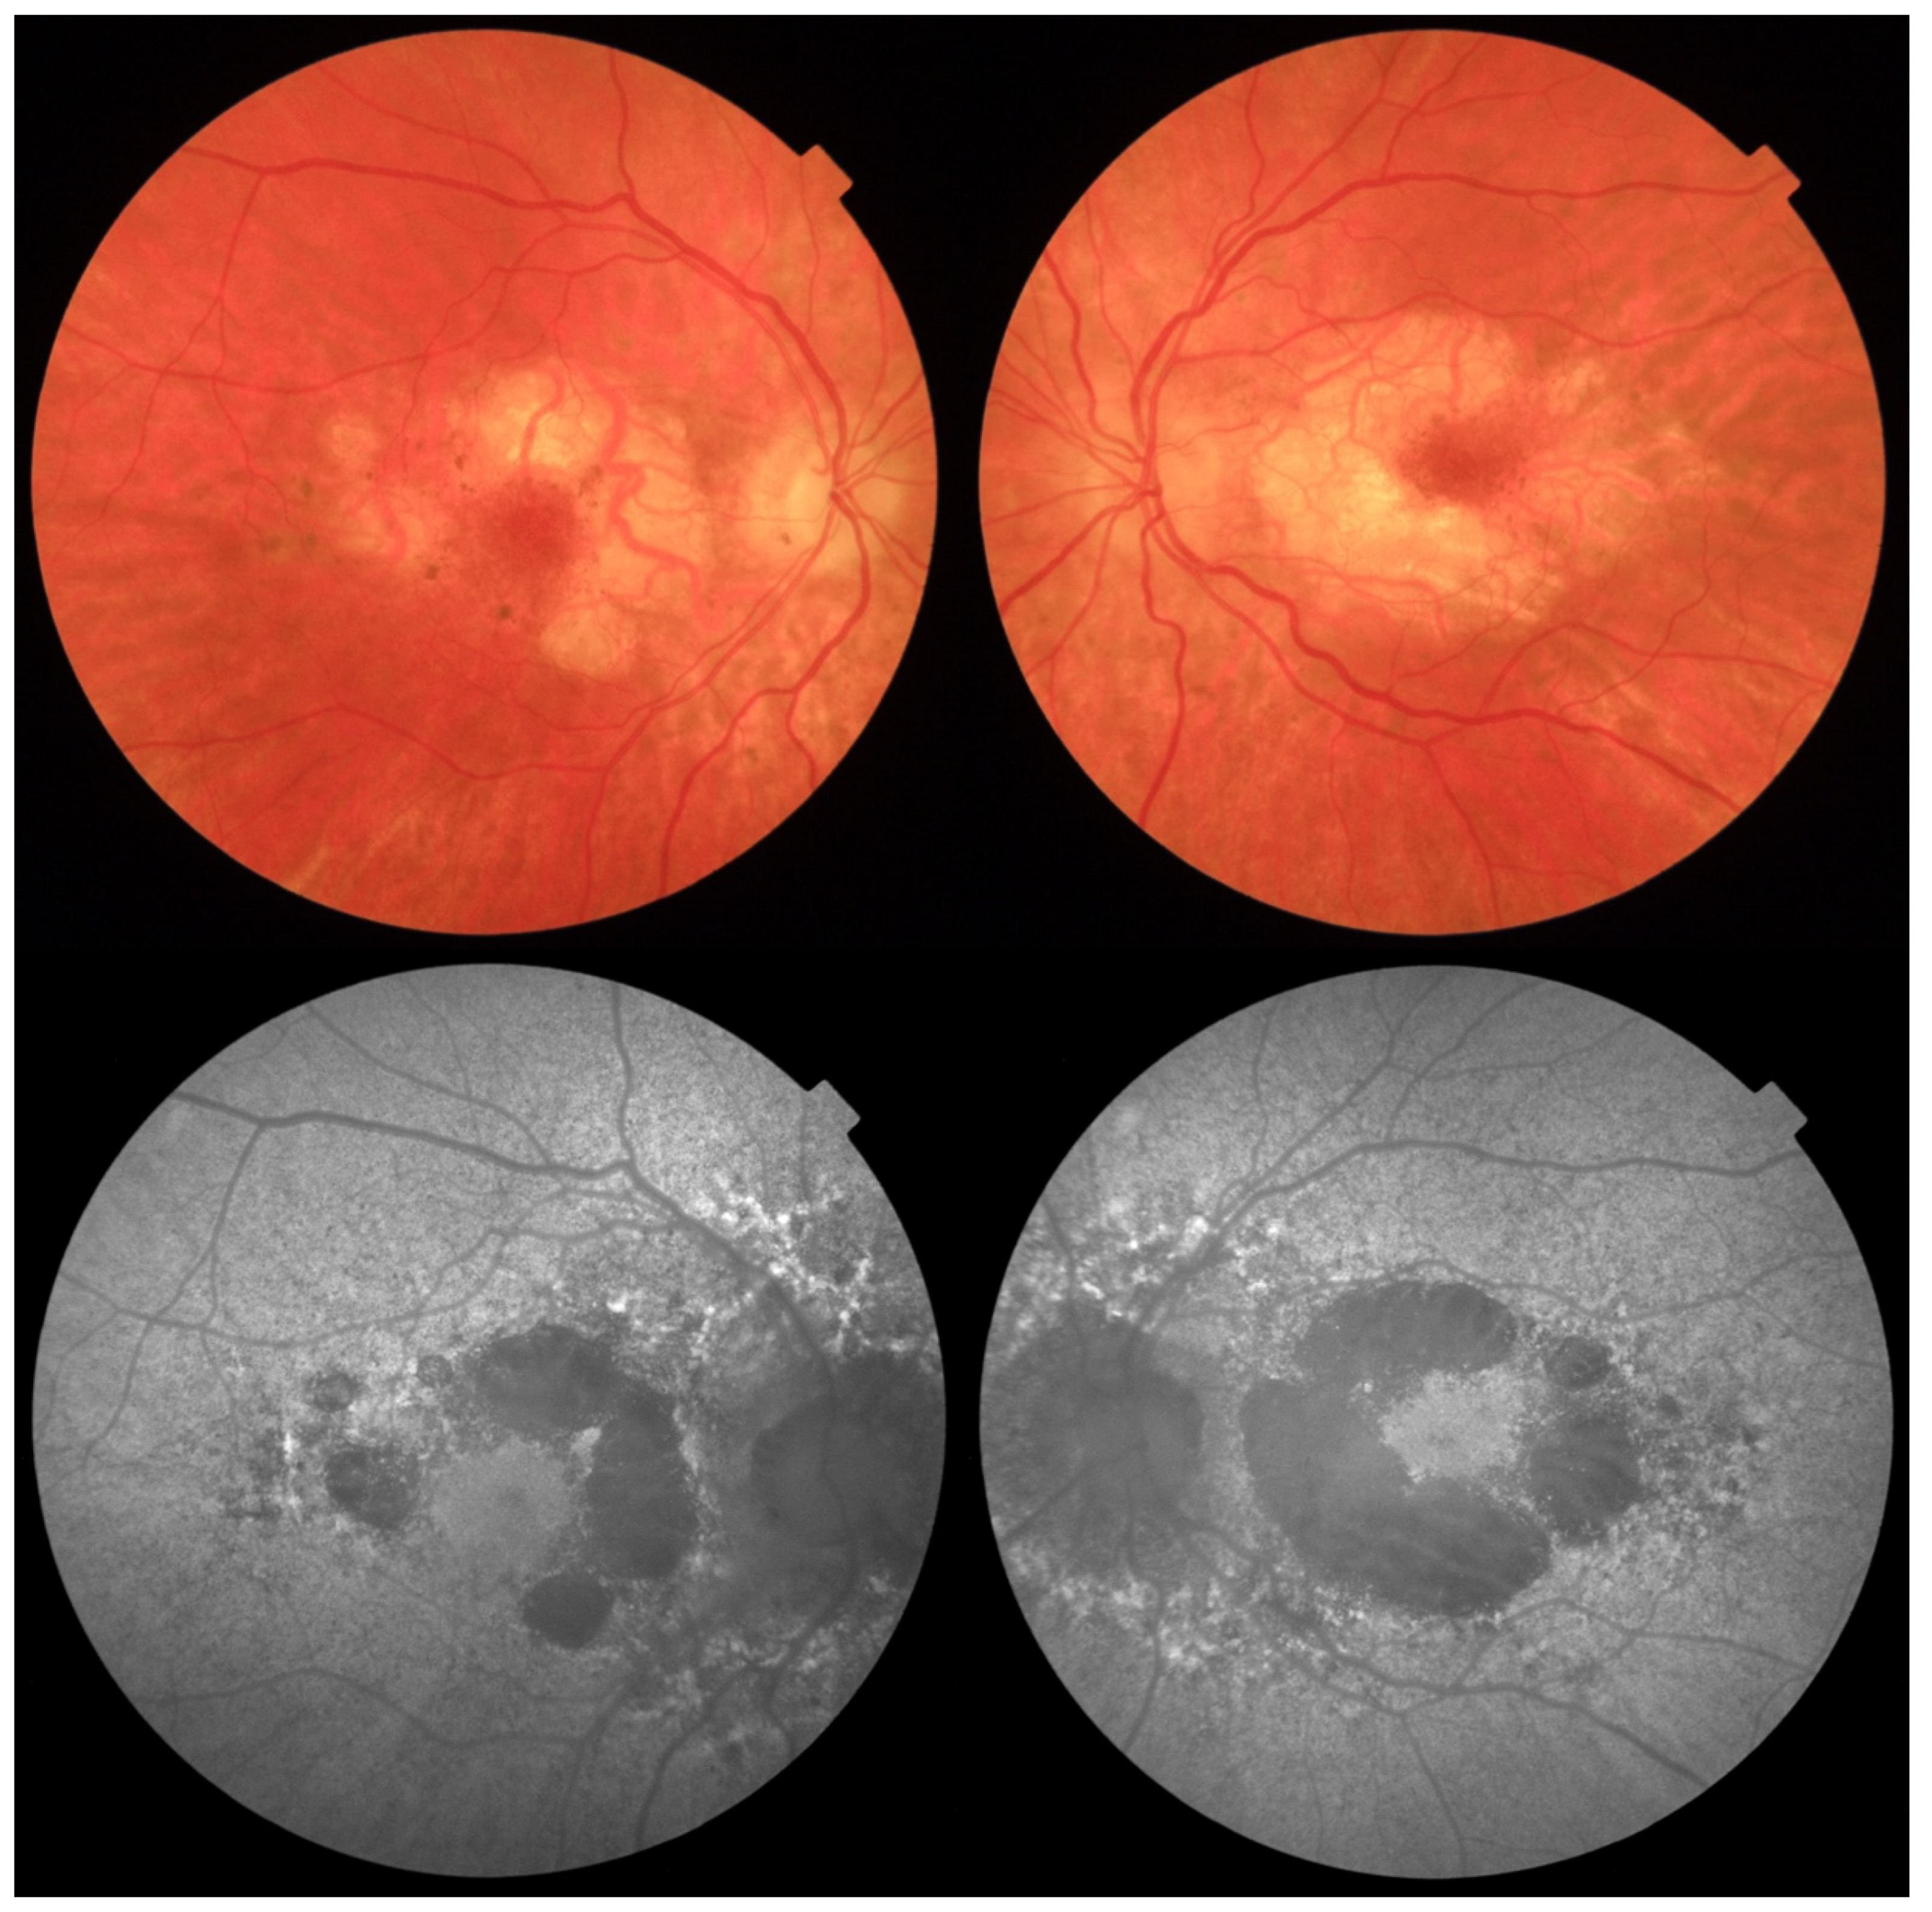

2. Case Report

Investigations and Results